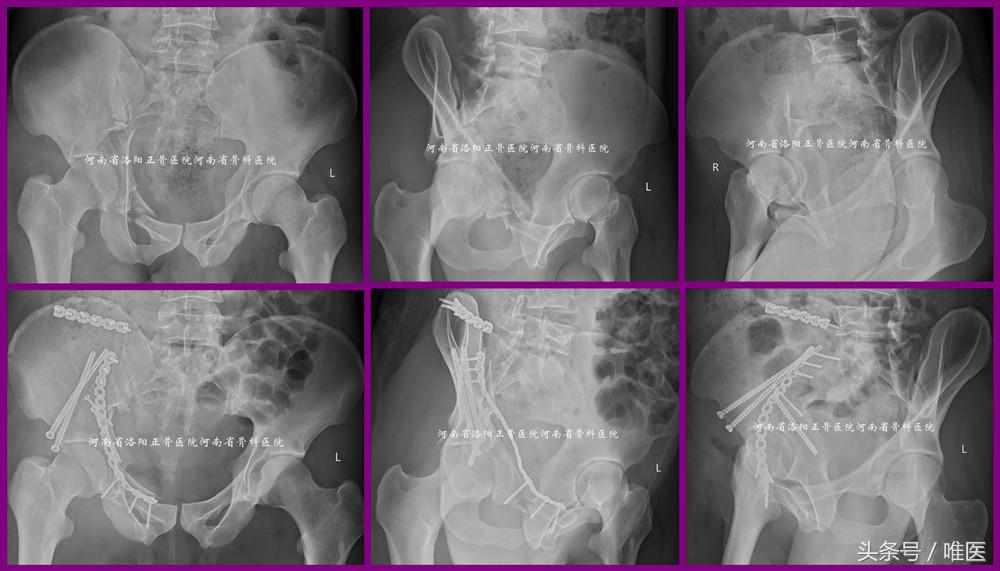

3. 用于治疗髋臼双柱骨折(即OTA-62C)的高位前柱骨折部

病例3:一例31岁男性病人,以高处坠落致右髋部疼痛活动受限两天入院。入院诊断:右侧髋臼骨折(OTA-62C1.2)。经髂腹股沟入路(ilioinguinal approach)显露骨折。先复位双柱骨折的高位前柱骨折部至主体骨并经皮置入两枚LC-II螺钉固定,然后应用Matta钳夹持复位后柱骨折部并经主体骨及复位后的高位前柱应用两枚螺钉固定,最后应用接骨板螺钉固定髋臼前柱的低位骨折部。术前及术后影像资料见图13。

图13. LC-II螺钉用于固定髋臼双柱骨折(即OTA-62C)的高位前柱骨折部。